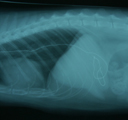

ペルシャ、オス、9歳。体重4.40kg。「本日朝に嘔吐を続けて6−7回あった」とのことで相武台動物病院を受診し、X線検査にてコード様の異物が食道から胃内にかけてあると診断された。

X線所見。食道から胃内にコード様の異物あり。 内視鏡所見。食道内にコード先端部が見えた。 内視鏡処置で先ず口の外まで出した。 異物は長さ30cmの「ねじりっこ」だった。